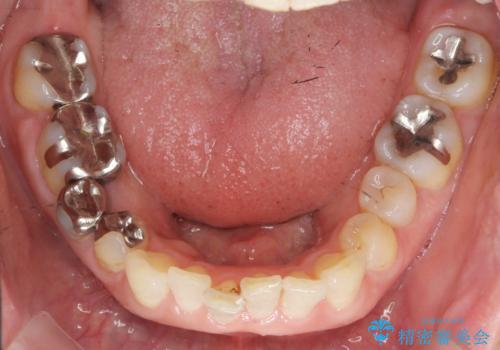

口腔内をメタルフリーにしたい

- 「 銀歯が原因で皮膚にアレルギー症状が出ている。」、と皮膚科のかかりつけ医に言われメタルフリー治療を希望され来院されました。

拡大鏡下で丁寧に銀歯の除去を行ったのち、金属を用いないセラミックインレー・クラウンによる治療を行います。